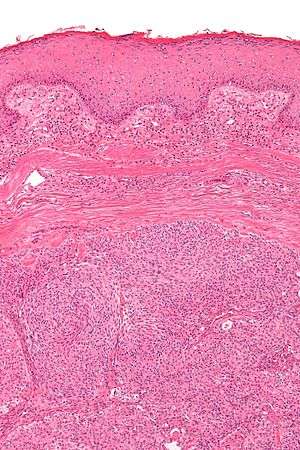

| Micrograph showing an acrospiroma. H&E stain. | |

Hidradenoma(also known as acrospiroma, from akral "peripheral" + spiroma "epithelial tumor of sweat gland") refers to a benign adnexal tumor of the apical sweat gland.[1][2] Another name for Hidradenoma is Cystadenoma and Hydrocystadenomas. These are 1–3 cm translucent blue cystic nodules.It usually presents as a single, small skin-colored lesion, and is considered distinct from the closely related poroma. Hidradenomas are often sub-classified based on subtle histologic differences, for example: